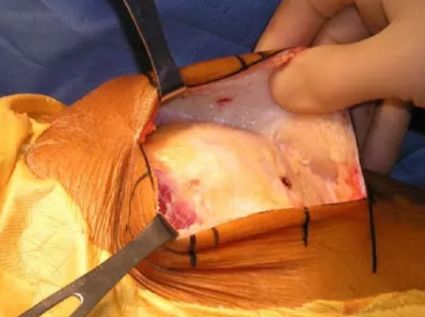

患者仰卧位,自股骨外上髁至腓骨颈做一纵向切口。

切开股二头肌肌腱(前)和腓总神经之间的深筋膜。

显露腓总神经,股二头肌牵向外侧,腓总神经牵向内侧。

复位和临时固定。